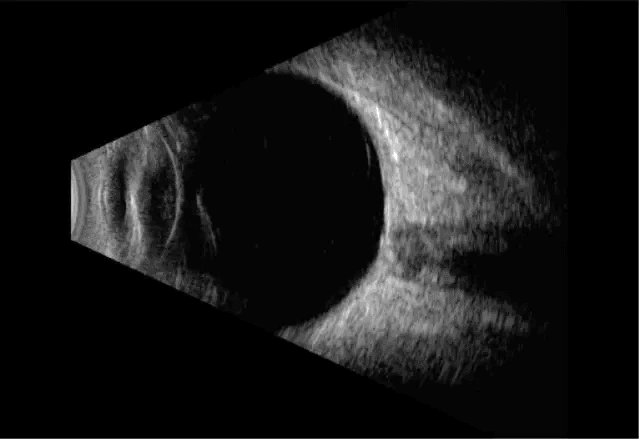

Ecografía ocular

Utiliza ultrasonido para evaluar el interior del ojo cuando no es posible observar bien el fondo ocular, por ejemplo en cataratas densas.

Ecografía ocular modo B